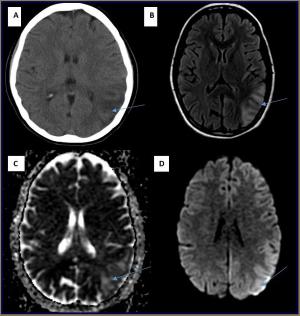

Diagnosing and Treating MELAS: Issues for Clinicians

ByAnkita Ghosh, MD,Mary Kay Koenig, MD

Differential diagnosis and treatment of mitochondrial encephalomyopathy lactic acidosis and stroke-like syndrome.